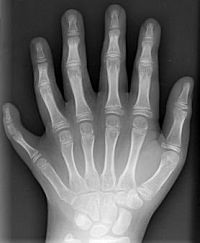

Polydaktilie

Abb. 8: Polydaktylie der linken Hand eines Kindes

Bildquelle: Polydactyly 01 Lhand AP.jpg von en:User:Drgnu23, subsequently altered by en:user:Grendelkhan, en:user: Raul654, and en:user:Solipsist. (Eigenes Werk) [GFDL oder CC-BY-SA-3.0], via Wikimedia Commons

Weitere Erkrankungen sind die Kurzfingrigkeit (Brachydaktylie), bei der eine Mutation zur Verkürzung einzelner oder mehrerer Finger führt, und die Vielfingrigkeit (Polydaktylie, Abb. 8), bei der es zur Ausbildung zusätzlicher Finger kommt.